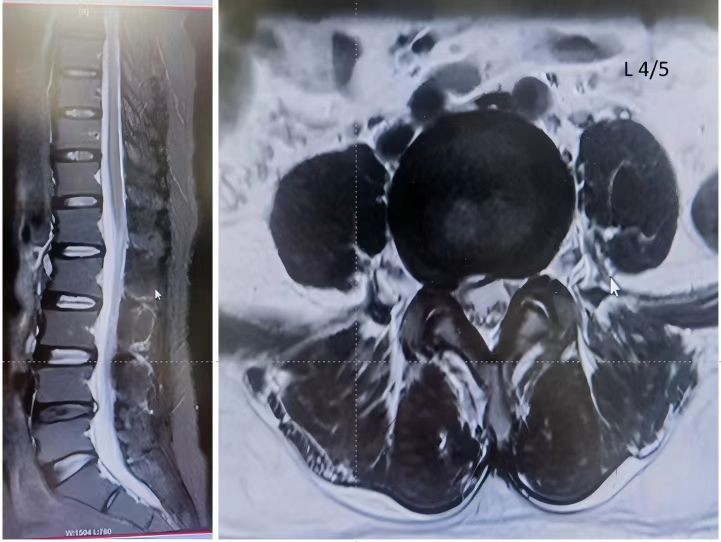

51岁的张大姐被腰腿疼痛折磨了好长一段时间,试了各种保守治疗都不见好转。片子显示腰4-5椎管狭窄、腰4退变性后滑脱症、腰4-5退变性不稳症等,要做传统开刀手术的话,伤口大、恢复慢,让她纠结了好久~